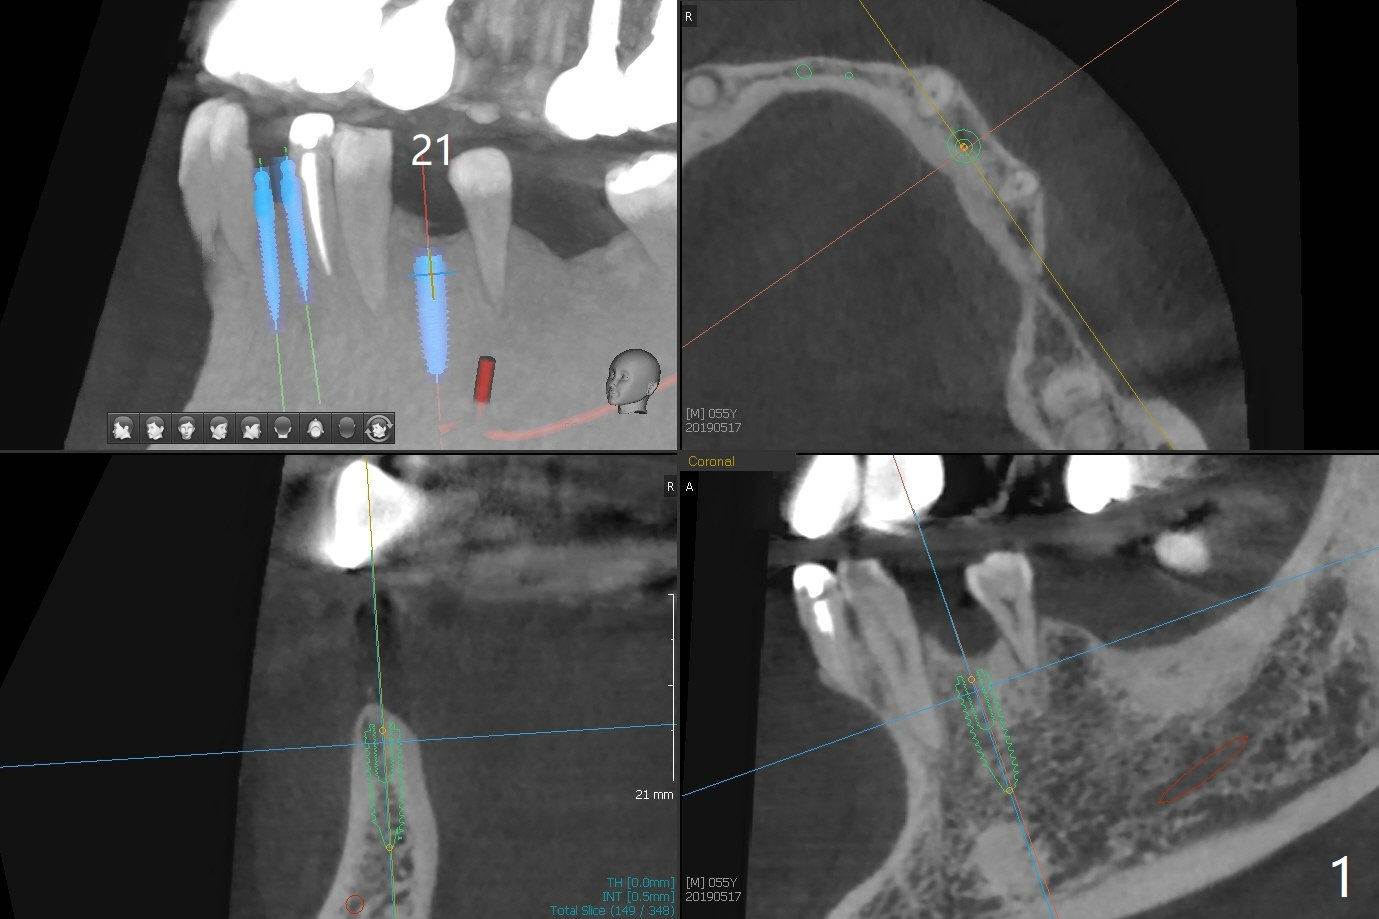

The implants at #11, 14 and 15 are IBS. To reduce the chance of screw loosening, IS guide will be used for better trajectory at #19,21,30. Since the ridge at #21 and 19 is pointed at the top, the implant will be placed deep (Fig.1-4). Bone trimmer will be used prior to pointed drill to avoid drill deflection. Check whether the IS implant driver fits IBS implant well. Try dummy implants first.